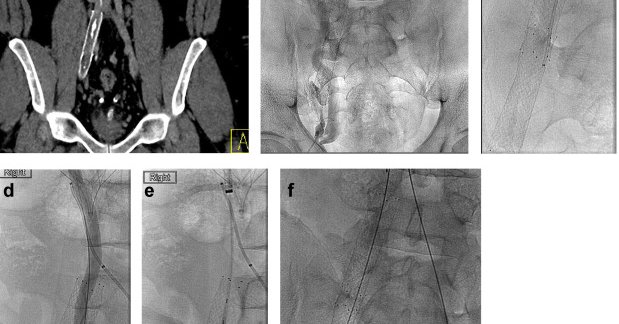

π©»β οΈ Rare vascular culprit. A middle-aged man with calf claudication was found to have a thrombosed true external iliac artery aneurysm from cystic media necrosis. Open repair achieved excellent results. π https://t.co/9GBuhyEArX

Aneurysms of the external iliac artery are extremely rare. We present a case of a middle-aged male patient with calf claudication owing to peripheral arterial embolism on the basis of a thrombosed...